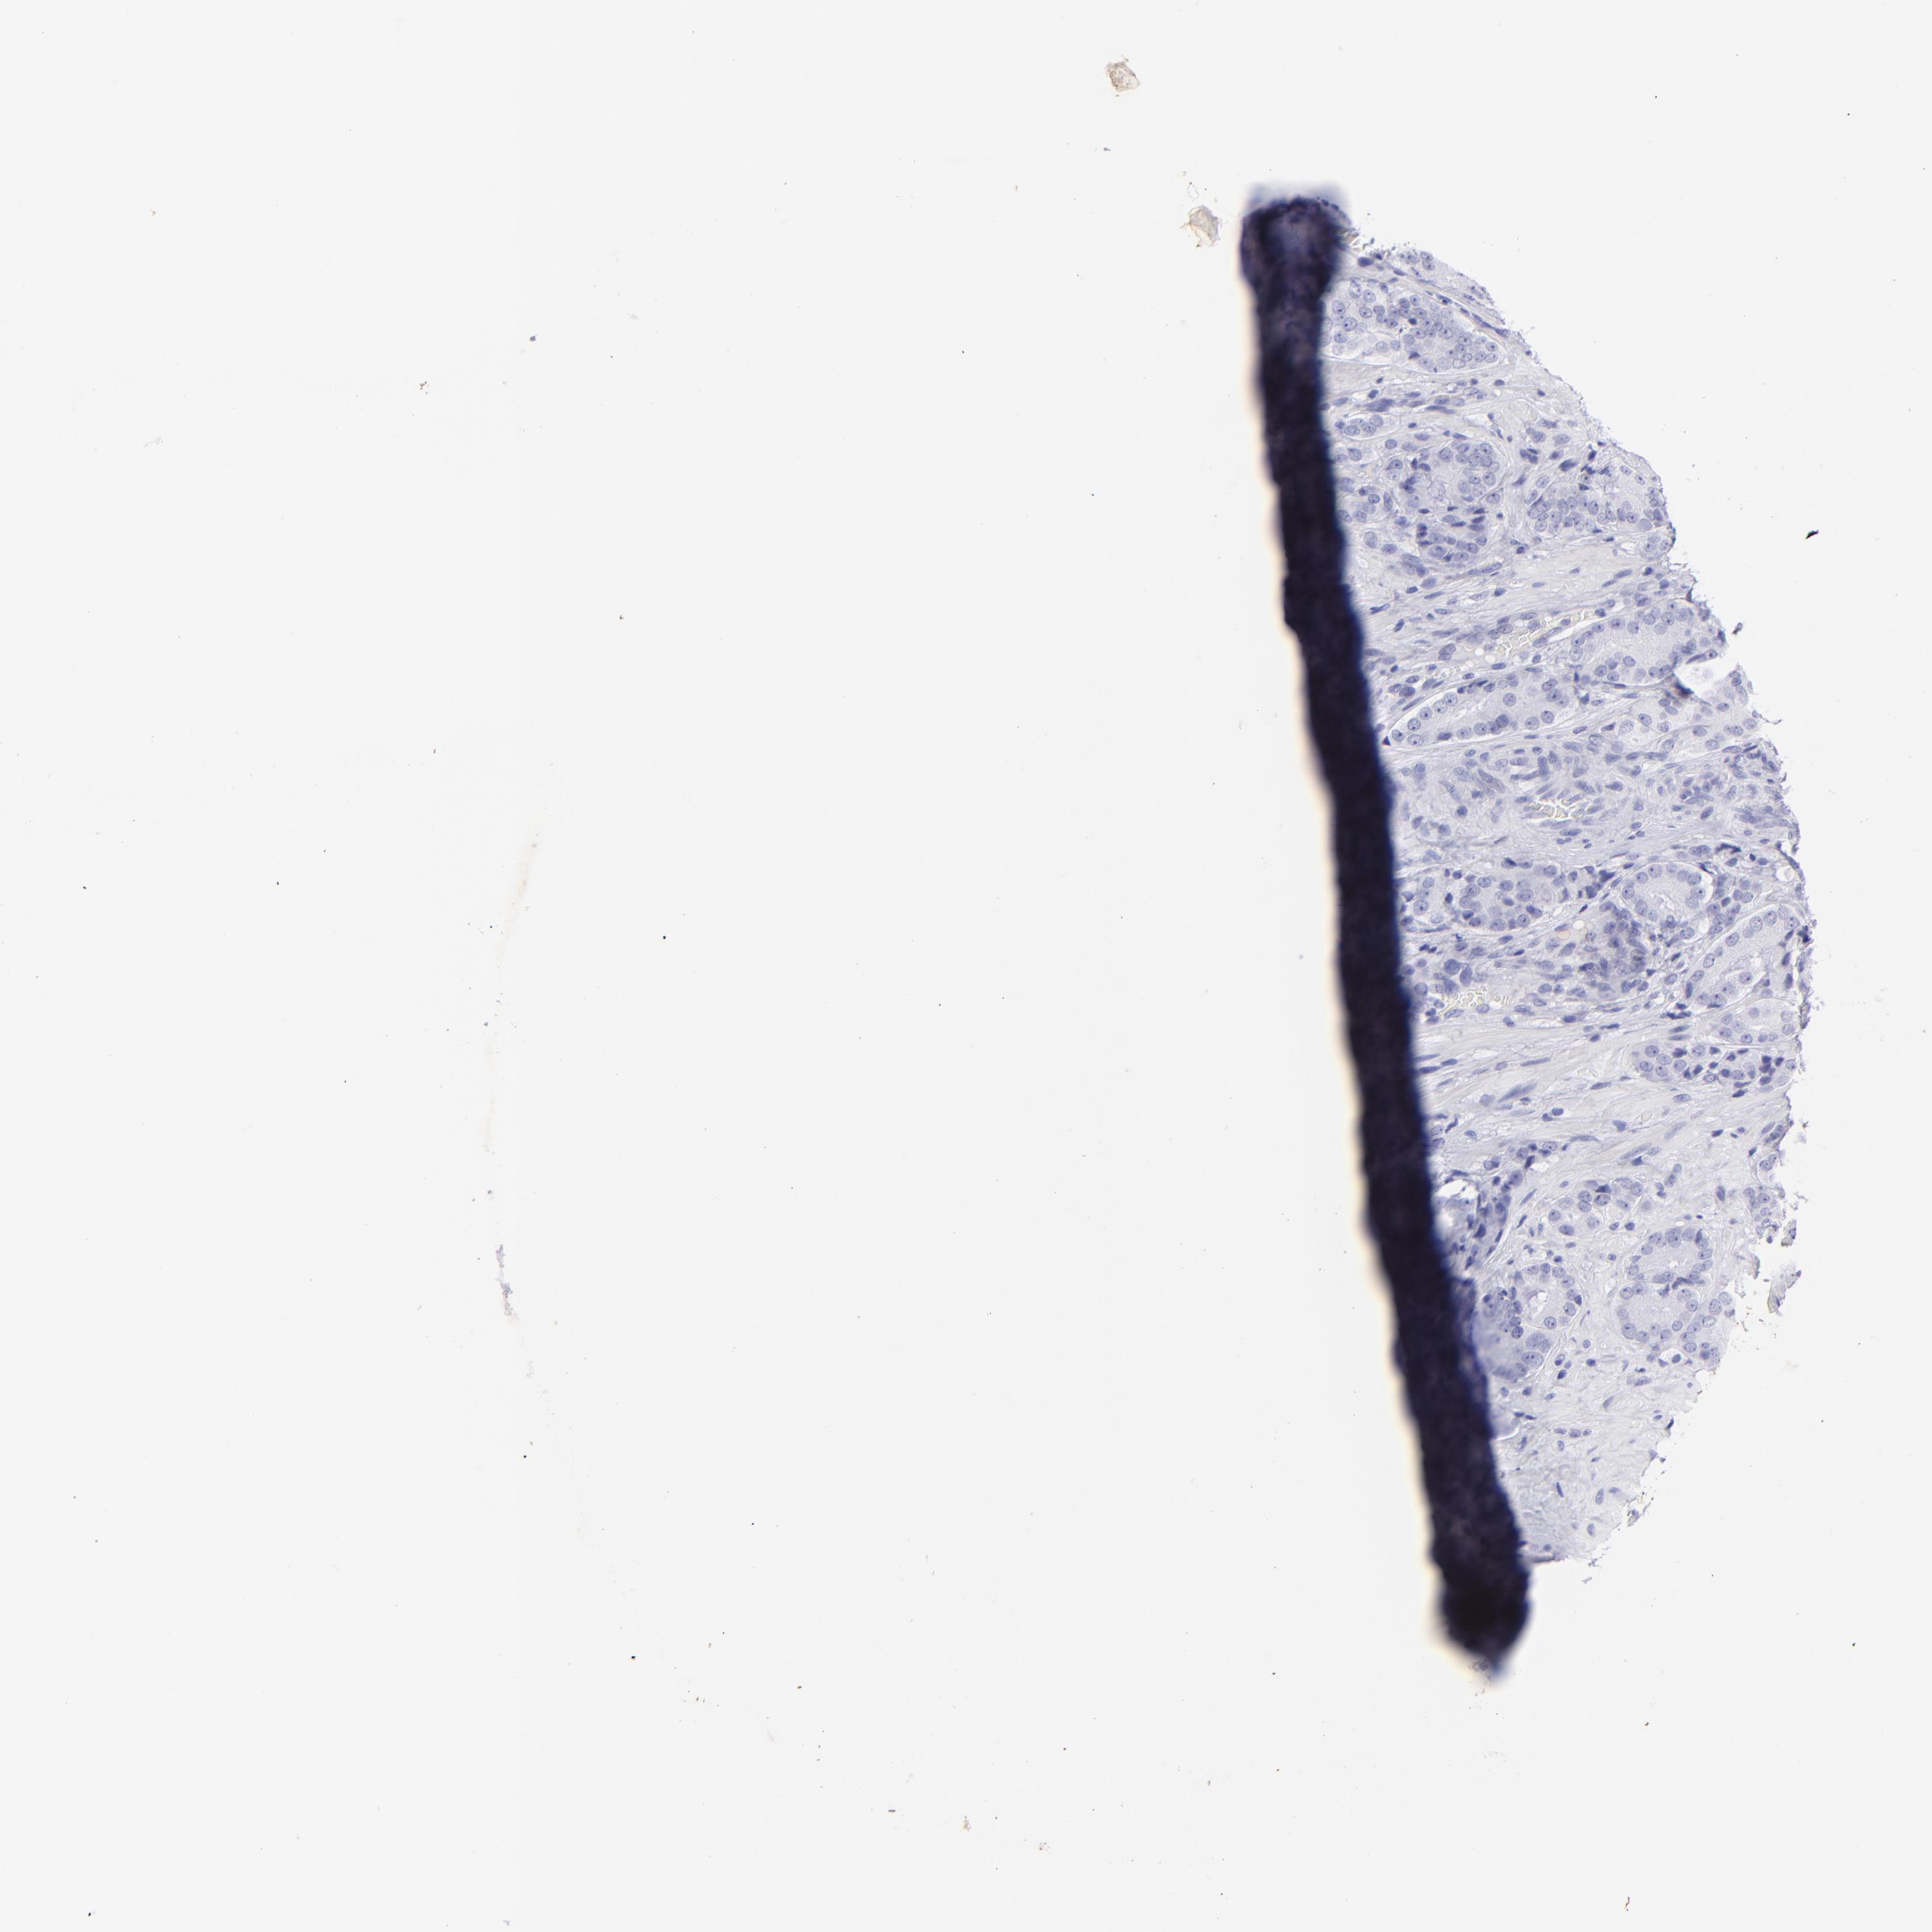

PROSTATE CANCER - Protein expressioni

A mouse-over function shows sample information and annotation data. Click on an image to view it in a full screen mode. Samples can be filtered based on level of antibody staining by selecting one or several of the following categories: high, medium, low and not detected. The assay and annotation is described here.

Note that samples used for immunohistochemistry by the Human Protein Atlas do not correspond to samples in the TCGA dataset.

Antibody stainingi

Antibody staining in the annotated cell types in the current human tissue is reported as not detected, low, medium, or high, based on conventional immunohistochemistry profiling in selected tissues. This score is based on the combination of the staining intensity and fraction of stained cells.

Each image is clickable and will lead to virtual microscopy that enables deeper exploration of all samples and also displays staining intensity scores, fraction scores and subcellular localization as well as patient and tissue information for each sample.

Antibody HPA009177

Antibody CAB002661

Adenocarcinoma, Low grade

Adenocarcinoma, High grade

Adenocarcinoma, Medium grade